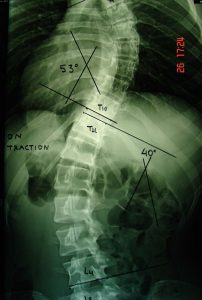

Εικόνα 4, α,β

Προεγχειρητικές δυναμικές ακτινογραφίες της Σπονδυλικής Στήλης, προς τα αριστερά (α) και υπό έλξη (β). Διαπιστώνεται ότι τα σπονδυλικά κυρτώματα είναι ιδιαιτέρως δύσκαμπτα, διότι διορθώνονται σε μικρό ποσοστό, σχεδόν 30%.